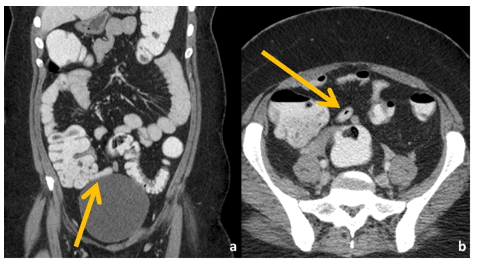

CT-RC proved to be as accurate as CT-IVRC in the diagnosis of AA. CT with rectal contrast alone could be performed in suspected cases of AA particularly in patients with contraindications to intravenous contrast administration.